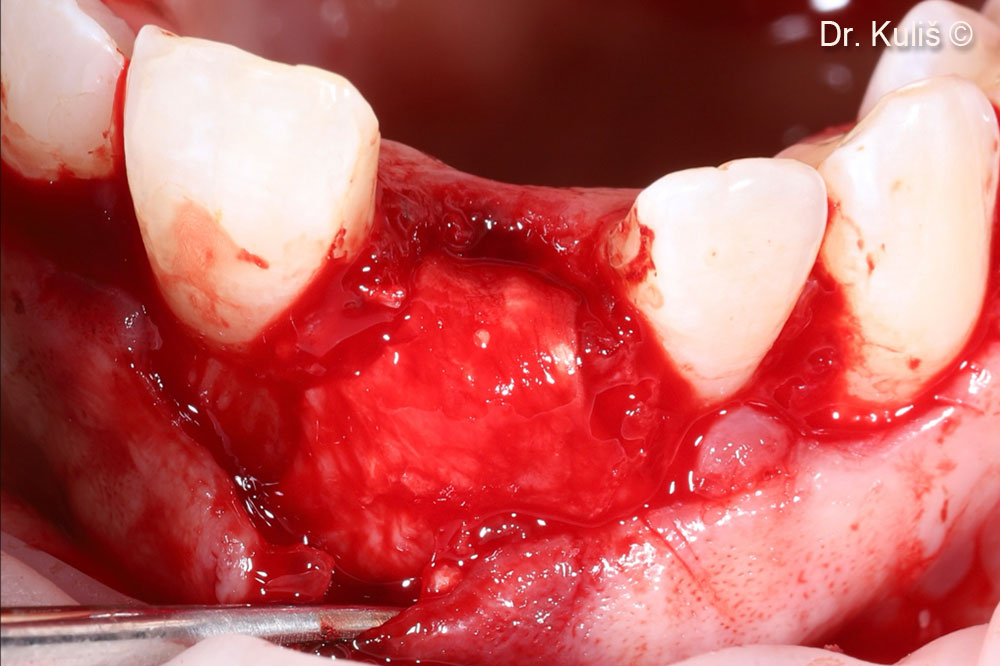

Khuyết tật xương má sau khi nhổ răng và loại bỏ mô hạt

Tăng cường xương bằng mp3®

Màng tế bào Evolution đã được điều chỉnh để phù hợp với khiếm khuyết.

Màng và lỗ của ổ nhổ răng được che phủ bằng vạt cuống vòm miệng.